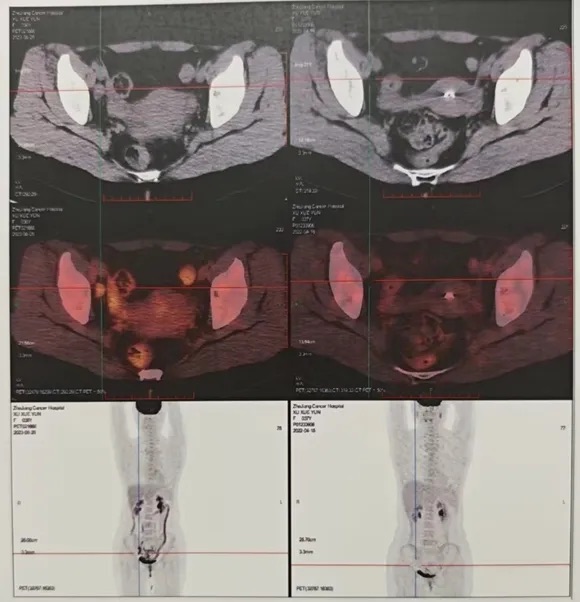

疗效评估及目前情况:回输后28天和3个月PET-CT疗效评估均为CR(CAR-T治疗前后PET-CT变化情况如图3-5),后续口服泽布替尼维持治疗。患者目前一般情况良好,骨髓抑制状态给予对症升白治疗。

图3 CAR-T治疗前:右侧髂血管旁多发肿大淋巴结,大者短径2.2cm,SUVmax7.5

图4 回输后28天:CAR-T治疗后,全身显像

未见高代谢灶,疗效评估:CR

图5 回输后3个月:CAR-T治疗后,全身显像未见高代谢灶,疗效评估:CR